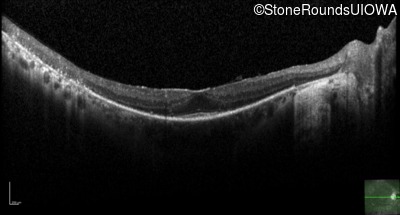

Optical Coherence Tomography - Right - 20/25 -2 sc

Exemplar / OCT Stack

OCT Stack